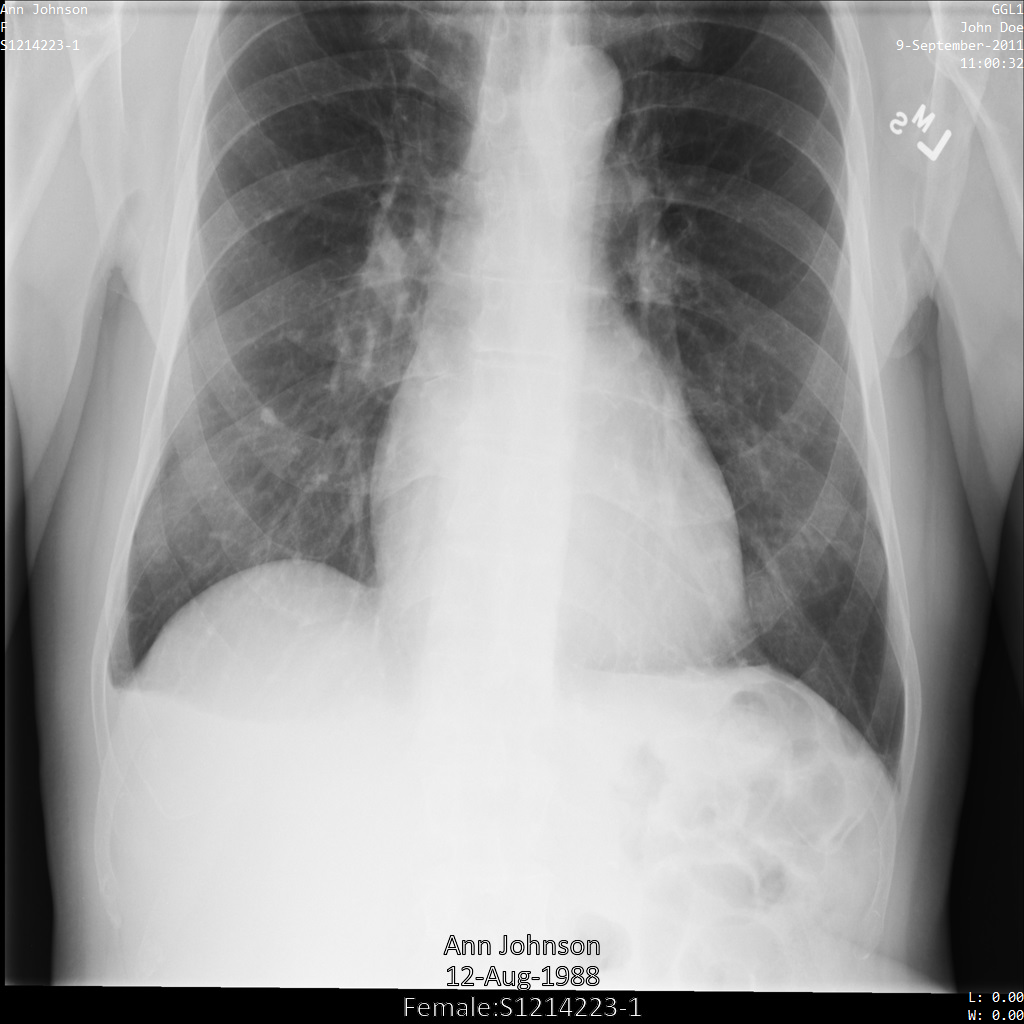

Les exemples suivants montrent comment anonymiser un ensemble de données contenant des magasins DICOM et des données DICOM à l'aide du profil de filtre de tag ATTRIBUTE_CONFIDENTIALITY_BASIC_PROFILE.

Ce profil de filtre de tag supprime les tags en fonction du profil de base de la confidentialité d'attribut du standard DICOM.

Une fois envoyée à l'API Cloud Healthcare à l'aide du profil de filtre de tag ATTRIBUTE_CONFIDENTIALITY_BASIC_PROFILE, l'image apparaît comme suit. Les métadonnées affichées dans les angles supérieurs de l'image ont été masquées, mais les données de santé incrustées en bas de l'image reste affichées.

Pour supprimer également le texte incrusté, consultez la section Masquer le texte incrusté dans les images.